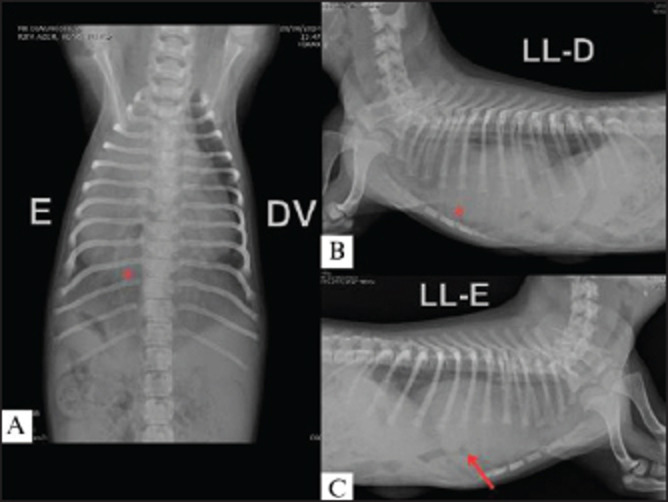

Case description: This article reports a case of PPH in association with a ventricular septal defect (VSD) in a pediatric canine patient. The dog, a female Shih Tzu, aged 2 months, presented with cyanosis, low weight, decreased body condition score (3/9), and underdevelopment in comparison with other puppies of the same litter. At physical examination, all parameters were within the normal range; however, there was a sound at the base of the heart during auscultation, and echocardiographic examination displayed VSD. Due to the dyspnea, thoracic radiography was performed, and the suspicion of PPH was confirmed. Peritoneopericardial hernioplasty surgery was indicated for a 2-month-old patient. During the surgical procedure, it was not necessary to enter the thoracic cavity in order to close the defect, and suture surgery was performed through the abdominal cavity accessed in the subxiphoidal region. Despite the high risks associated with the procedure, no intraoperative or anesthetic complications occurred.